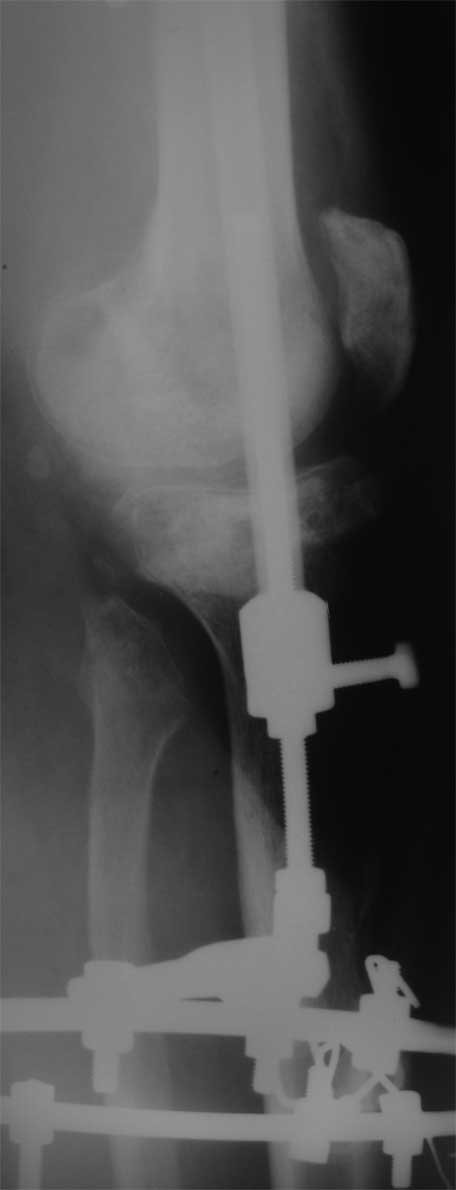

Я бы сделал пластику мягких тканей (торакодорзальный лоскут совместно с микрохирургами или пластику латеральной головкой икроножной мышцы) и выполнил бы краевой отщеп большеберцовой кости для его дистракции аппаратом в проксимальном направлении (рис. 1 – пример применения отщепа (авторство не мое), рис. 2 – схема предлагаемого варианта замещения дефекта кости).

2. Хотелось бы увидеть снимки раннего периода, лучше после травмы, а также КТ. Интересует целостность плато б/б кости. По представленным

снимкам возникает подозрение, что наружный мыщелок отделен. Или это так кажется?

> Хотелось бы увидеть снимки раннего периода, лучше после травмы, а также КТ. Интересует целостность плато б/б кости. По представленным

- нет, скорее всего не кажется, вероятно он отделен, но, скорее всего живой и неподвижный (иначе рассосался бы)